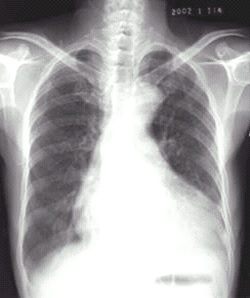

03卷-4.病史:女性,73歲,血壓升高10年,心悸、頭暈、乏力2周。診斷(本題滿分2.00分)

靴形心

B.靴形心

本題答案:B

題目解析:【該題針對“X線-心臟增大(二尖瓣型、主動脈型和普大型)”知識點進行考核】